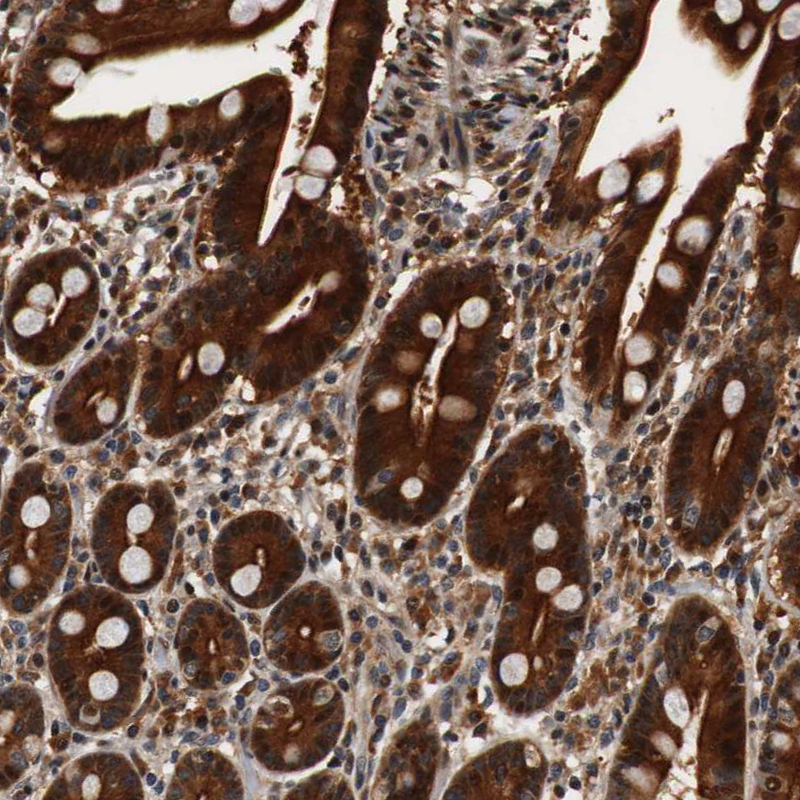

Immunohistochemical staining of human adrenal gland shows strong cytoplasmic positivity in glandular cells.